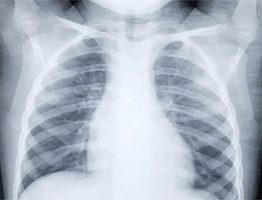

Il campanello d’allarme, secondo gli esperti, impone rigidi controlli che scattano ogni due anni soprattutto per quegli individui con pregresse storie di fratture. Il miglior metodo per tenere sotto controllo l’avanzare di queste malattie sistemiche dello scheletro è la diagnostica per immagini ai raggi X che valuta la densitometria ossea: in altre parole, l’esecuzione della MOC. Grazie a questo esame, infatti, possono essere individuati i principi di osteopenia e l’avanzamento dell’osteoporosi. Ma di cosa si tratta di preciso?

Sfrutta i raggi X per misurare i grammi di calcio e di altri minerali ossei accumulati nel segmento di un osso e individuare l’avanzamento dell’effetto spugnoso all’interno delle ossa.  Vengono scannerizzate dalla MOC la colonna vertebrale, l’anca e l’avambraccio.